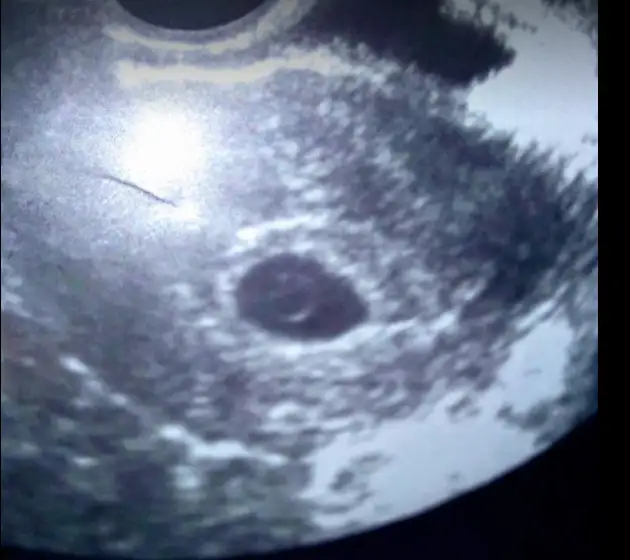

Kızlar bu ultrason görüntüsünde yolk sac üzerinde bebiş gören var mı? ben mi hayal görüyorum ??

ben 6 hafta 1 gunlukken gittimde bile kese bos gozukdu ust duzey ultrasyona alindim orada bile zor gozukdu doktor bu yuzden hafta tekrar cagirdu darlanma yani

Bizim sat aynı galiba canım 25 temmuz.. 15. gün çatladı yumurtam yani geç döllenme olduğunu düşünmüyorum. Bugün gripten dolayı gittim dr.a kese ve yolk sac göründü ama embriyo görünmedi. 4 gün önce bolu da bi lekelenme yaşadığım için kontrole gitmiştim orda bebek görünmüştü ama kalp atışı ancak haftaya duyulur demişti. Usg farkından mı kaynaklanıyor anlamadım ama kafam bayaa karıştı Hemşire düşük falan olsa kesede büzüşme olurdu gayet güzel görünüyor dedi.. Umudum haftaya kaldı anlayacağın..